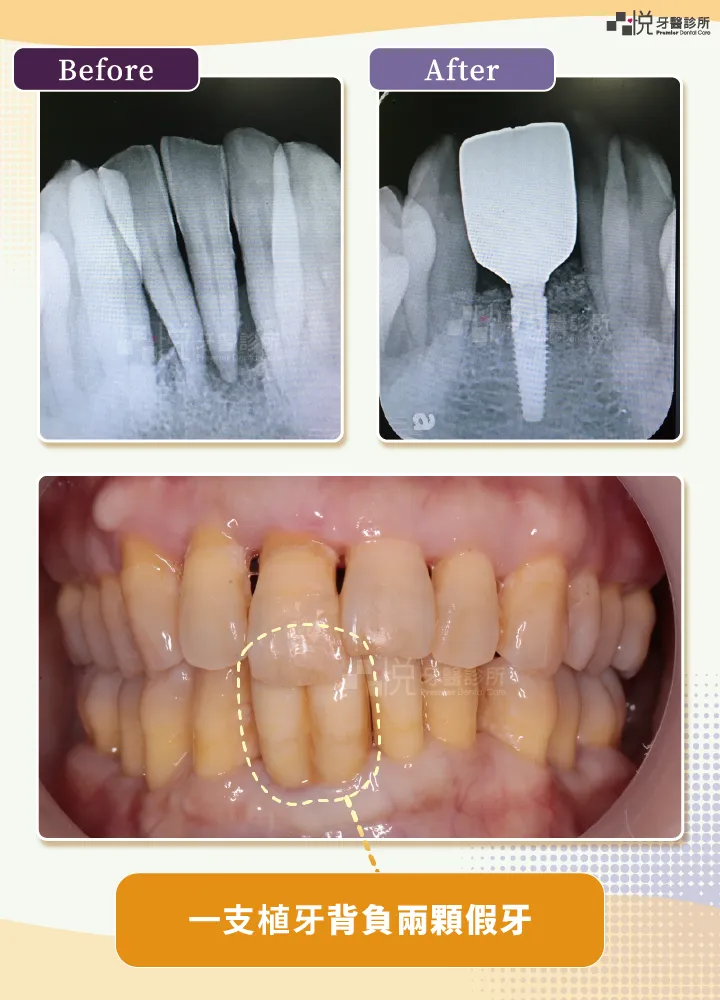

植牙手術完,憑空要從骨頭裡接出一顆假牙,讓假牙穿出牙肉,其實是需要一段時間來讓牙肉生長,觀察牙肉貼合植牙假牙的情況。

臨時假牙塑形後,牙肉會被撐開,呈現我們想要的樣子,尤其是前牙區域,一點點的牙齦厚度、高度,都是美麗笑容的關鍵。

由於每個人的牙肉狀況也有不同,用臨時假牙才能確保牙肉長成我們要的樣子,若不滿意,臨時假牙也有調整的空間。

有些植牙假牙會從內部過度擠壓牙肉,造成鎖得位置不對,或是牙肉發炎,有些又太瘦,支撐不了牙肉,以後容易從太細的地方斷裂。有了臨時假牙,這些問題都能提前發現並得到解決。